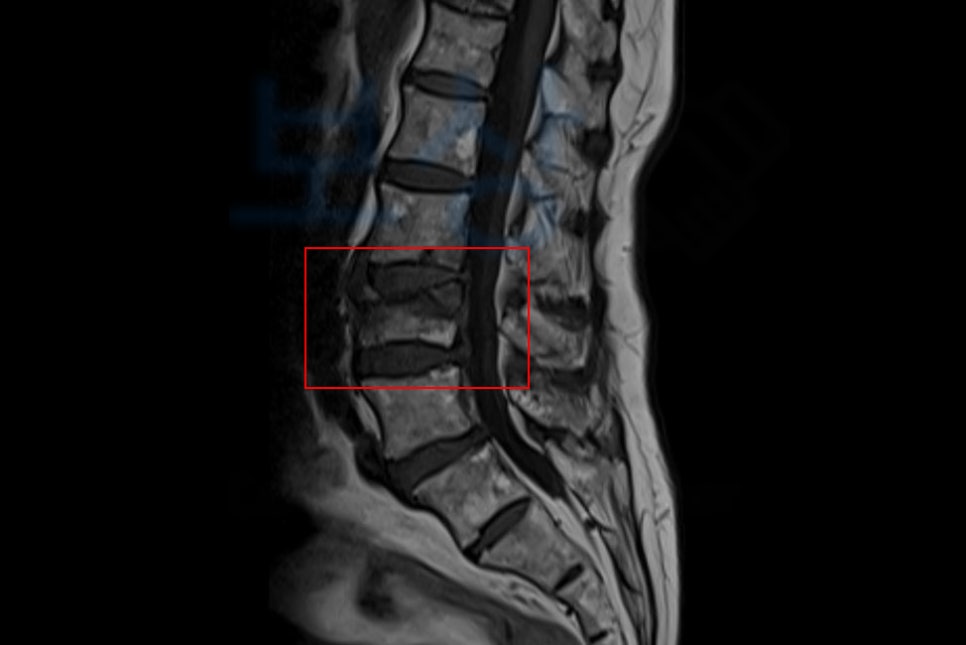

mri사진도 보시면 심각하게 척추체가 찌그러진 것을 보실 수 있죠. 이 사고로 주치의는 수술을 권유했으나, 척추에 수술을 하는 것에 대해 여러 이유로 수술보다는 보존치료를 선택하셨는데요,

김@@님의 보험증권과, 영상CD를 보며 어느정도의 보상 가능성을 예측한 뒤 공신력있는 의료 전문의로부터 보험사 약관에 명시된** AMA방식의 ** 후유장해진단서를 발급받았습니다.

발급된 후유장해진단서를 기초로 손해사정서를 작성하여 증명 서류와 함께 각 보험사로 송부하였죠. 물론 보험사에서는 전문의마다 측정시 발생하는 차이를 근거로 들며 보험금 삭감을 진행하려 했지만 약 한달간의 분쟁이 오간 뒤 결국 저희가 처음 청구한 척추의 약간의 기형 15% 지급율 모두 인정받아 후유장해보험금으로 총 1,200만원 지급받았습니다.